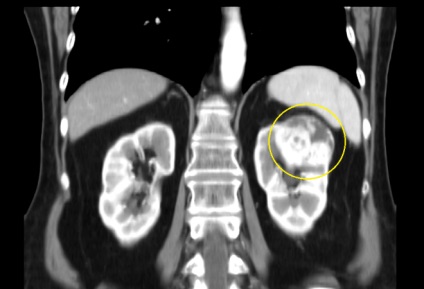

- chisturi renale Patologie sunt considerate a fi anormală creșterea acestuia în dimensiune. Medicina, există cazuri în care chisturi parenchimatoase a ajuns la 10 cm sau mai mult în diametru. chist parenchimul renal lăsat ce este, atunci când tumora este crescut? La această dimensiune a chistului garantat perturba organele interne, ceea ce duce la inflamații și boli infecțioase ale cavității abdominale.

- chist parenchimul renal se poate rupe în timpul creșterii lor, având ca rezultat scurgerea de fluid din corpul tumorii în cavitatea sau canalul zona mochetochnyh peritoneală. Când rupe chisturile persoana bolnavă se confruntă cu dureri de tăiere severă în abdomen sau partea inferioara a spatelui. Alte caracteristici ale rupturii chistului sunt atacuri de febră, greață, indigestie, creșterea tensiunii arteriale.